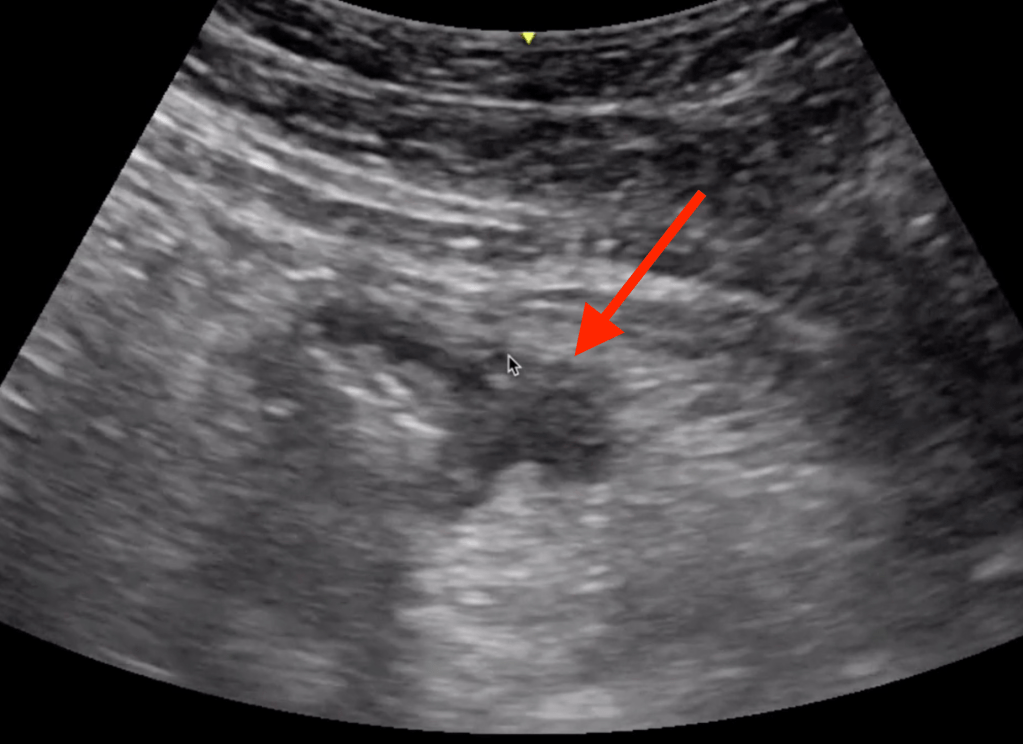

5 Minute Sono

- Large curvilinear probe

- Graded compression up and down

- Diverticula

- Bowel wall>5mm

- Prominent fluid-filled bowel loops

- Pericolic free fluid

- Increased pericolic fat (hyperechoic)

- Abscess